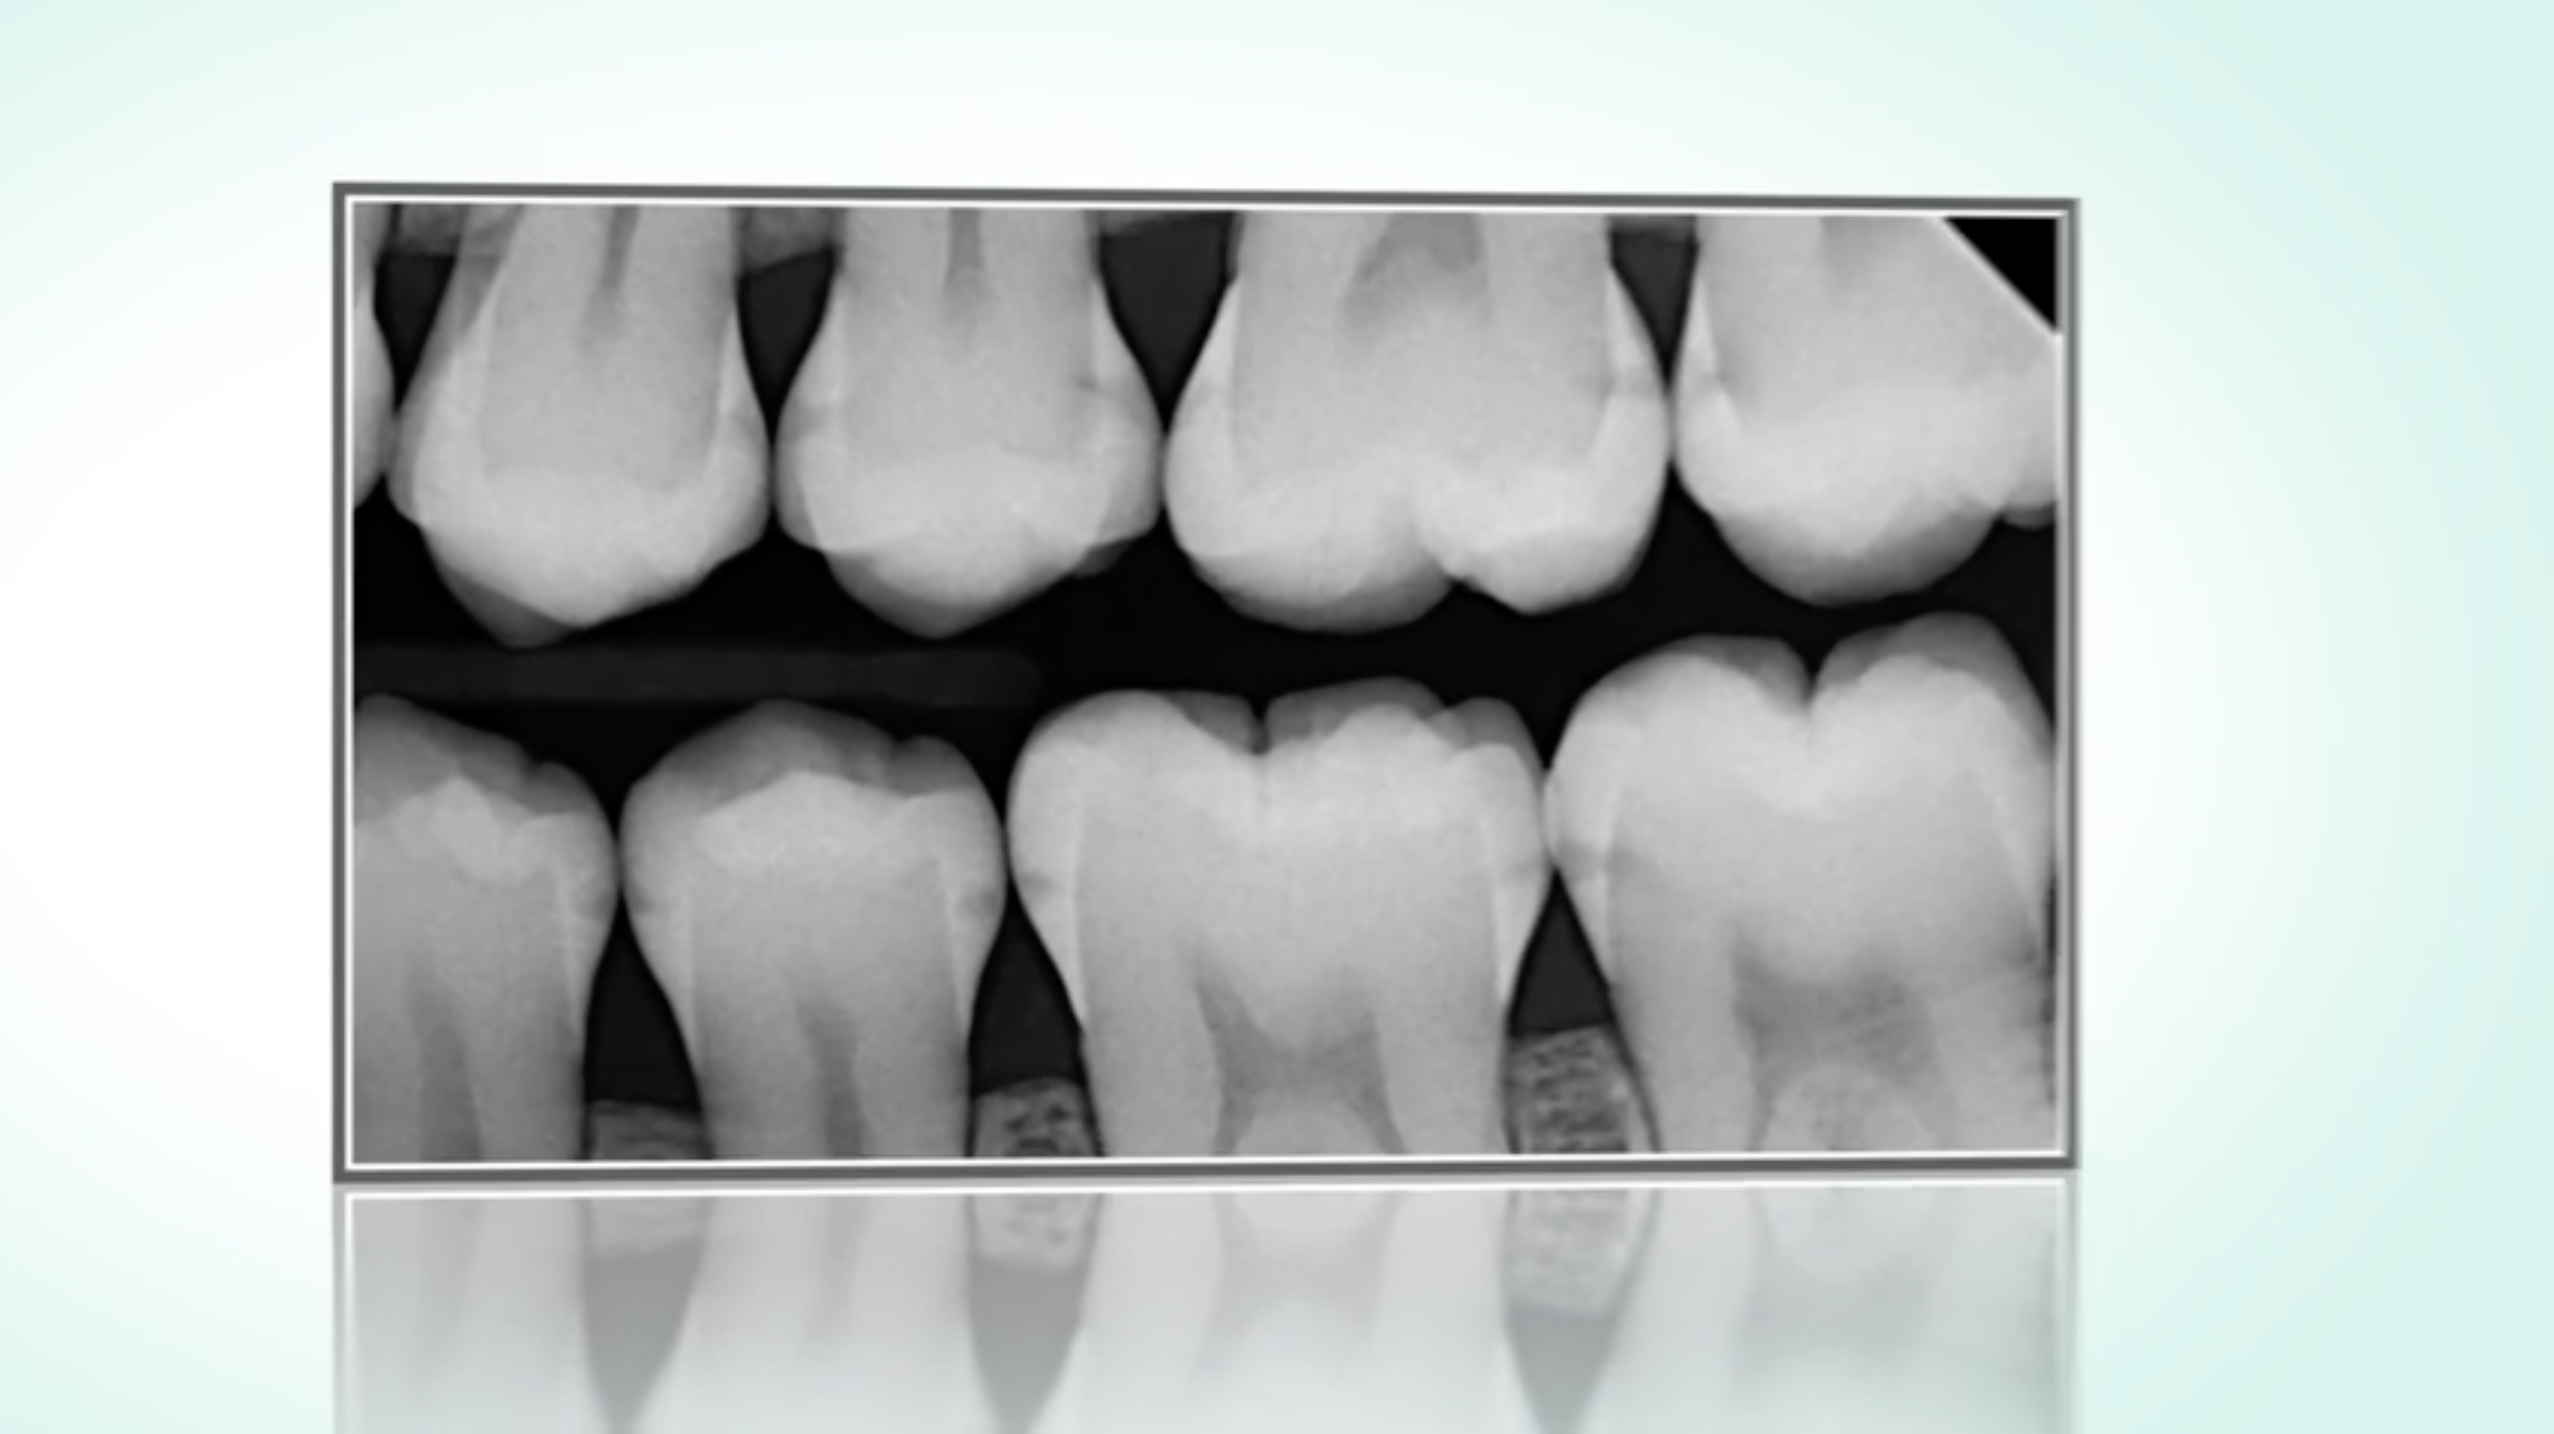

Was tun bei beginnender Karies im Zahnzwischenraum?